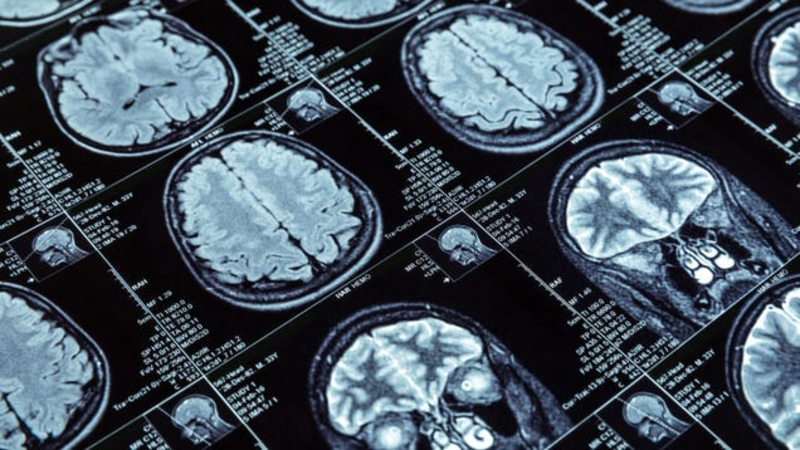

New research seems to offer some long-sought insights into the perplexing and devastating condition known as myalgic encephalomyelitis, also called chronic fatigue syndrome. The National Institutes of Health-led study found several potentially key differences in the brains and immune systems of people with ME/CFS…